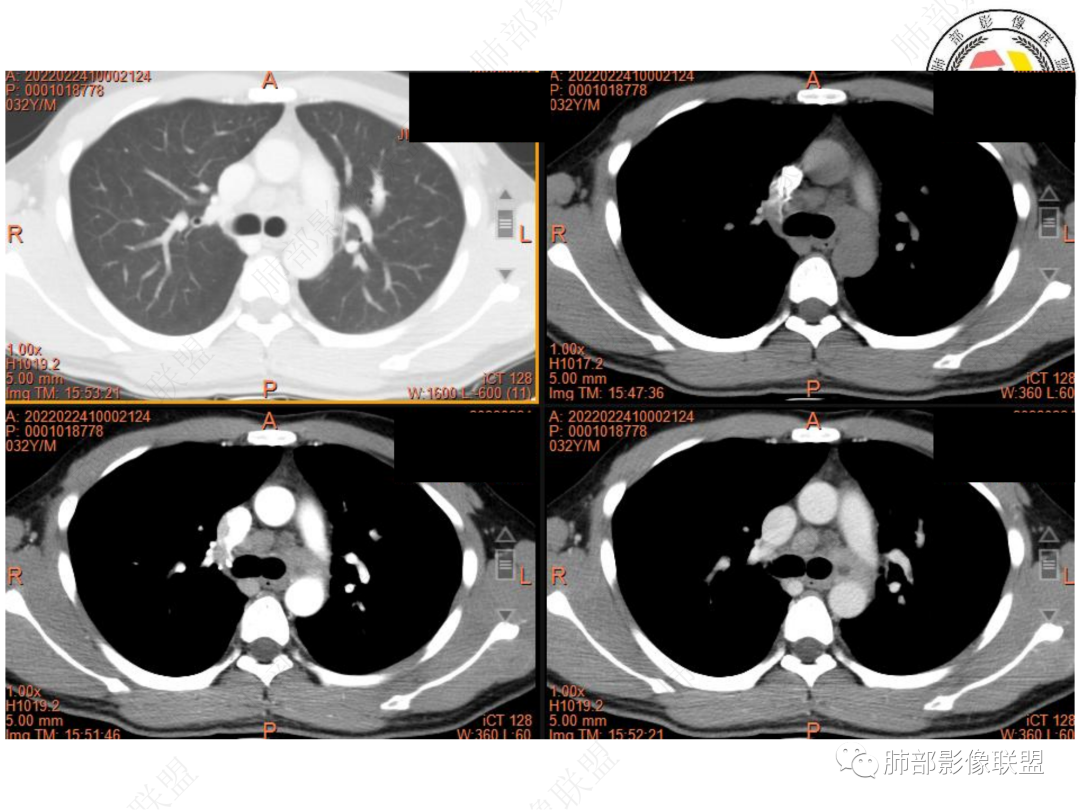

1. 青年男性,偶然发现左肺下叶结节影,左肺门及纵隔内多发淋巴结肿大,并坏死。

2. 肿瘤标志物及结核相关检查均为阴性。

3. CT示左肺下叶背段孤立实性密度结节影,边缘比较清楚光滑,总体呈现膨隆感,未见分叶毛刺,少张力,部分层面病灶边缘呈现较清楚磨玻璃样密度影,并于磨玻璃影病灶内可见多发小空泡,未见钙化或空洞,增强后病灶显示不均匀强化,未见低密度液化区。未见卫星病灶。

左肺门及纵隔内多发淋巴结肿大,大部分淋巴结显示融合,强化不均匀,内见低密度区,疑液化坏死。纵隔内淋巴结部分周围脂肪间隙不清晰。大血管及左肺主支气管未见受侵改变。

5. 此病例青年男性,纵隔淋巴结环形强化,易先入为主诊断结核。但左肺下叶背段病灶密度均匀,强化明显,整体具备膨隆感,缺少炎性病灶的平直征,病灶周围未见卫星灶,应想到新生物可能。纵隔及左肺门肿大淋巴结,虽有部分淋巴结环形强化特点,但是部分淋巴结周围血管脂肪间隙小时、密度增高,强化明显。至此,亦可与结核的环形强化区分开来。尽管患者年轻,但恶性征象出现时,仍应当高度警惕。